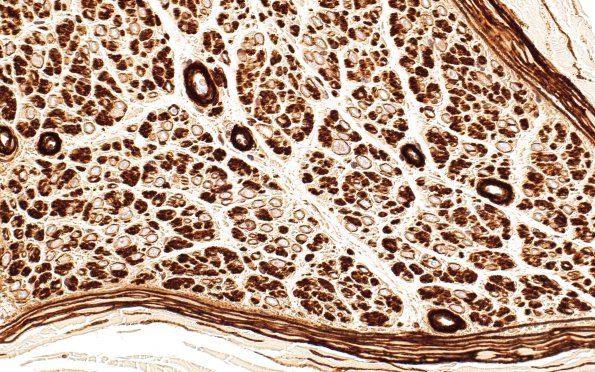

Collagen IV stains basement membranes of vessels, perineurium and Schwann cells of both myelinated and unmyelinated axons. (Coll IV IHC)